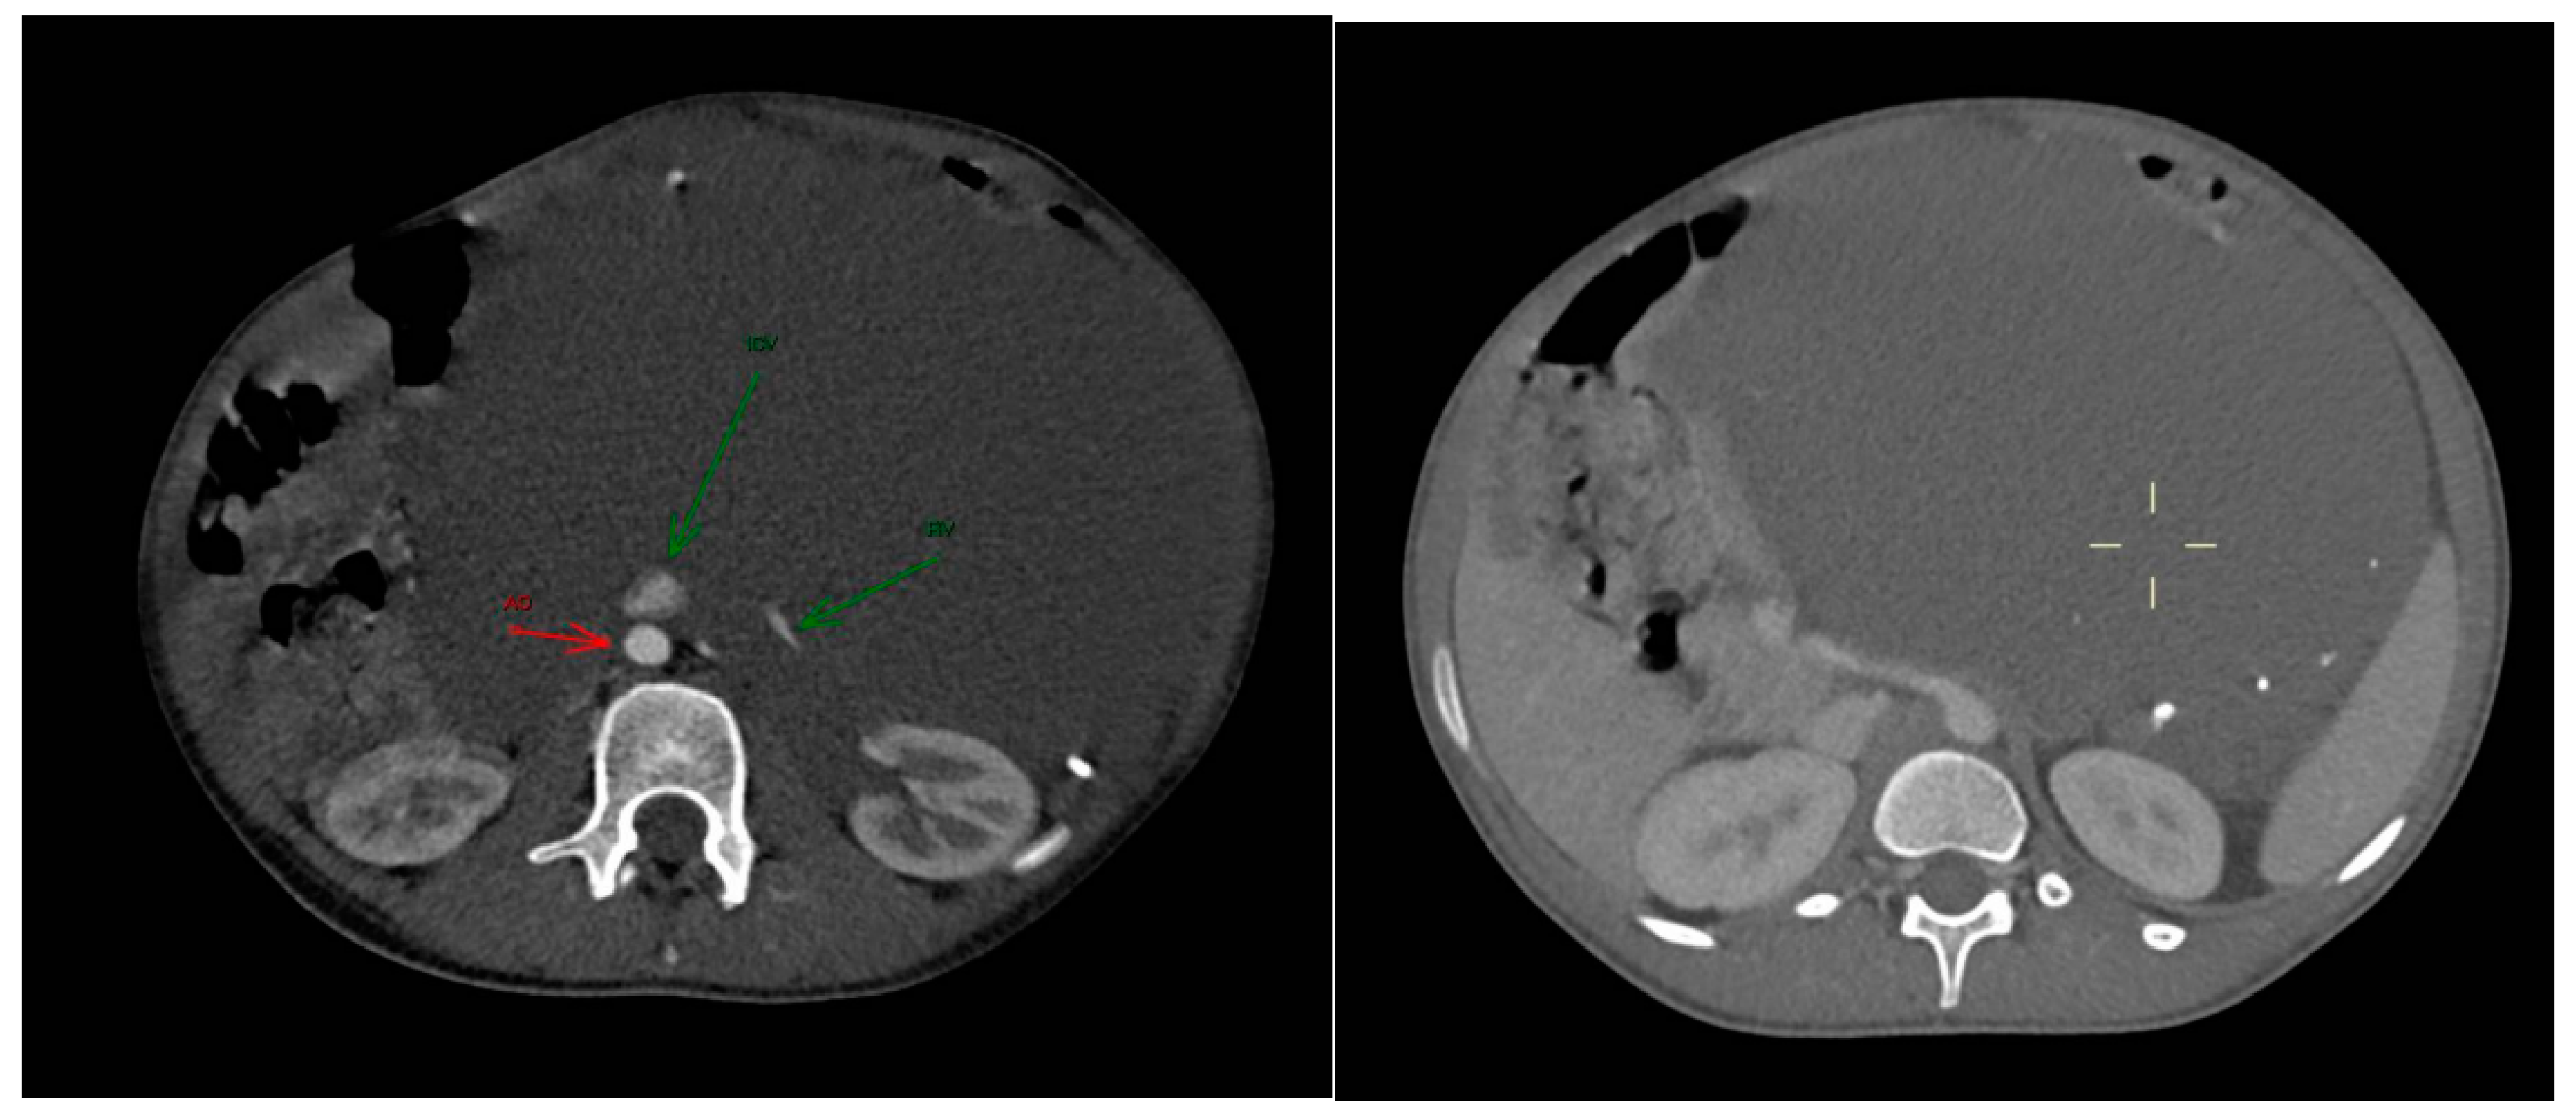

Figure 1. The axial post-contrast CT in the arterious (a) and portovenous (b) phase reveals the full extent of the mass and its intra-peritoneal location, without infiltration of the adjacent structures. The mass contains calcified density components, which were later identified as phleboliths. (a): green arrows indicated Renal Vein (RV) and Inferior Vena Cava (ICV); red arrow indicated the Aorta (AO).

An ultrasound examination was performed with the visualization of a multiloculated lesion, characterized by anechoic and hypoechoic cystic spaces separated by thin septations, with moderate intralesional vascularization at color-doppler evaluation. Then, a second level imaging with contrast-enhanced CT scan of the abdomen was performed, revealing a intraperitoneal large, multiseptated hypodense mass containing multiple calcified components (Figure 1), measuring approximately 21 × 16 cm in the axial plane and extending up to 30 cm in the sagittal plane. The lesion occupied nearly the entire abdominal cavity, predominantly on the left side, compressing adjacent structures. It wrapped smoothly around the left kidney and adrenal gland, displacing bowel loops and other abdominal organs, with a poorly defined interface with the surrounding tissues.

The major abdominal vessels, including the celiac trunk, superior mesenteric artery, inferior mesenteric artery, and the inferior vena cava as well as both renal veins and arteries were compressed with a partial course within the mass itself. However, no evidence of vascular compromise was observed.